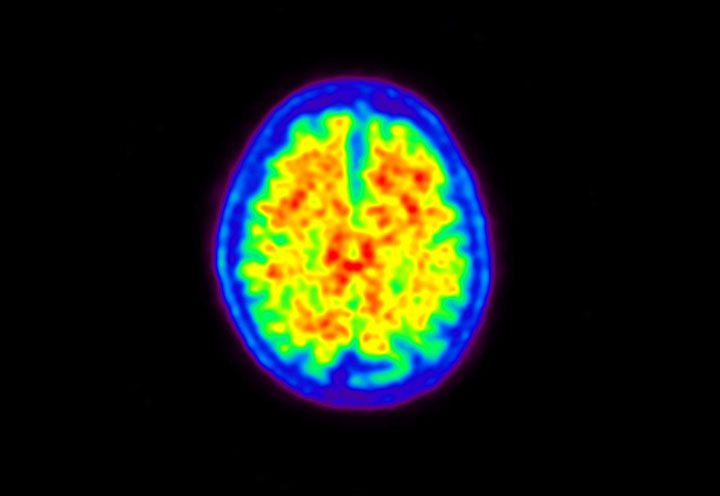

Head / Case5 : Amyloid

Axial

Courtesy : Kindai University Hospital

- Imaging protocol

- Injected dose: 4.27 MBq/kg, 18F-Flutemetamol

- Uptake time: 99 minutes

- Scan time: 20 minutes